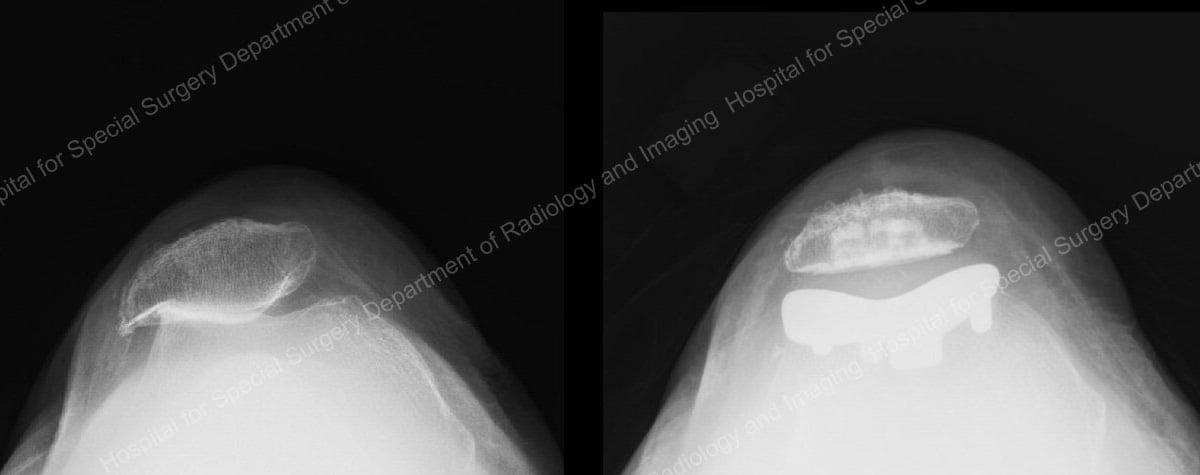

X-rays of patellofemoral arthritis (left) and the joint after patellofemoral knee replacement.

During this procedure the orthopedic surgeon removes the damaged cartilage and a small amount of bone from the joint surface of the patella and replaces it with a cemented high-density plastic button or patella implant. Damaged cartilage and a small amount of bone are also removed from the joint surface of the trochlear groove, which is replaced with a very thin, metal laminate which is cemented in place. “The goal is to eliminate friction and restore a smoothly gliding motion in the joint,” Dr. Beth Shubin Stein explains.